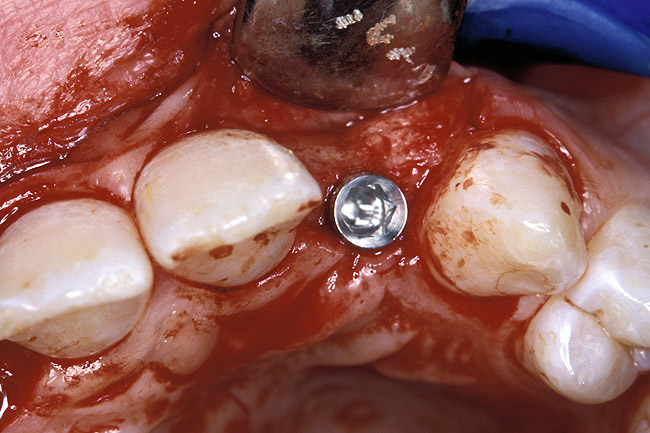

Before the day of surgery, the patient was seen by the orthodontist for the removal of the orthodontic brackets. The patient still was not pleased with the position of the two centrals, and it was determined that this would be addressed after implant placement (Figure 13A). The anatomical variations of the crestal tissue and lack of interdental papilla can be appreciated in the close-up views of the right and left sites (Figure 13B and 13C). There were no surprises on the day of surgery as all of the decisions were made during the planning phase, before the scalpel ever touched the patient. The occlusal view of the CT 3D model revealed the wider alveolar ridge on the right side and thinner crest on the left side (Figure 14A). This was confirmed when the full thickness mucoperiosteal flaps were elevated, and the underyling bone revealed (Figure 14B). The tooth-borne templates were designed to facilitate the drills and drilling sequence specific to the diameters of the predetermined implants (Figure 15A). Each template contained an embedded 5-mm long stainless steel tube, which was approximately 0.2-mm wider than each drill (just wide enough to allow for the drills to rotate freely). Once positioned over the natural teeth, the template was secure and offered precision accuracy in transferring the implant locations from the original software-designed plan, allowing the potential for internal and external irrigation (Figure 15B). The 3.7-mm diameter Tapered Screw-Vent implant drilling sequence requires three drills: pilot, intermediate, and final sizing. Thus, three separate templates were fabricated to a.commodate these sizes. The templates were removed easily and replaced with the next sequential size in less time than it takes to change the drill on the surgical handpiece. After the osteotomies had been.completed, the implants were delivered to the site (Figure 16A and Figure 16B). For this internal hex connection implant, the author r.commends that the flat of the antirotational hex be positioned to the facial for proper orientation of the restorative.components (Figure 17A). Preprepared margins were created from a milled titanium fixture mount transfer post, which was delivered to the implant as support for an immediate transitional restoration. The facial “dot” helped confirm the orientation of the abutment to the facially positioned flat side of the internal hex connection (Figure 17B). Before cementation of the transitional acrylic restorations, a closed-tray, fixture-level impression was made, and a soft-tissue model fabricated.

Figure 16a  After (A) the osteotomies were completed, (B) the implants were placed.

Figure 16a

Figure 16b  After (A) the osteotomies were completed, (B) the implants were placed.

Figure 16b